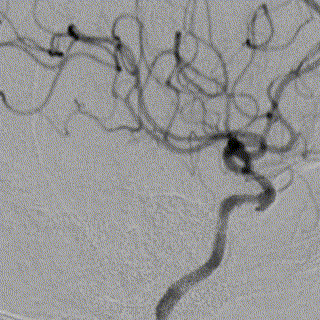

脑血管造影提示右侧颈内动脉颅内段多发动脉瘤(反主动脉弓)

脑血管造影提示右侧颈内动脉颅内段多发动脉瘤

4mm×30mm Streamline

术后4月余随访:多发动脉瘤均未见显影,远端残余轻度狭窄

术前术后对比